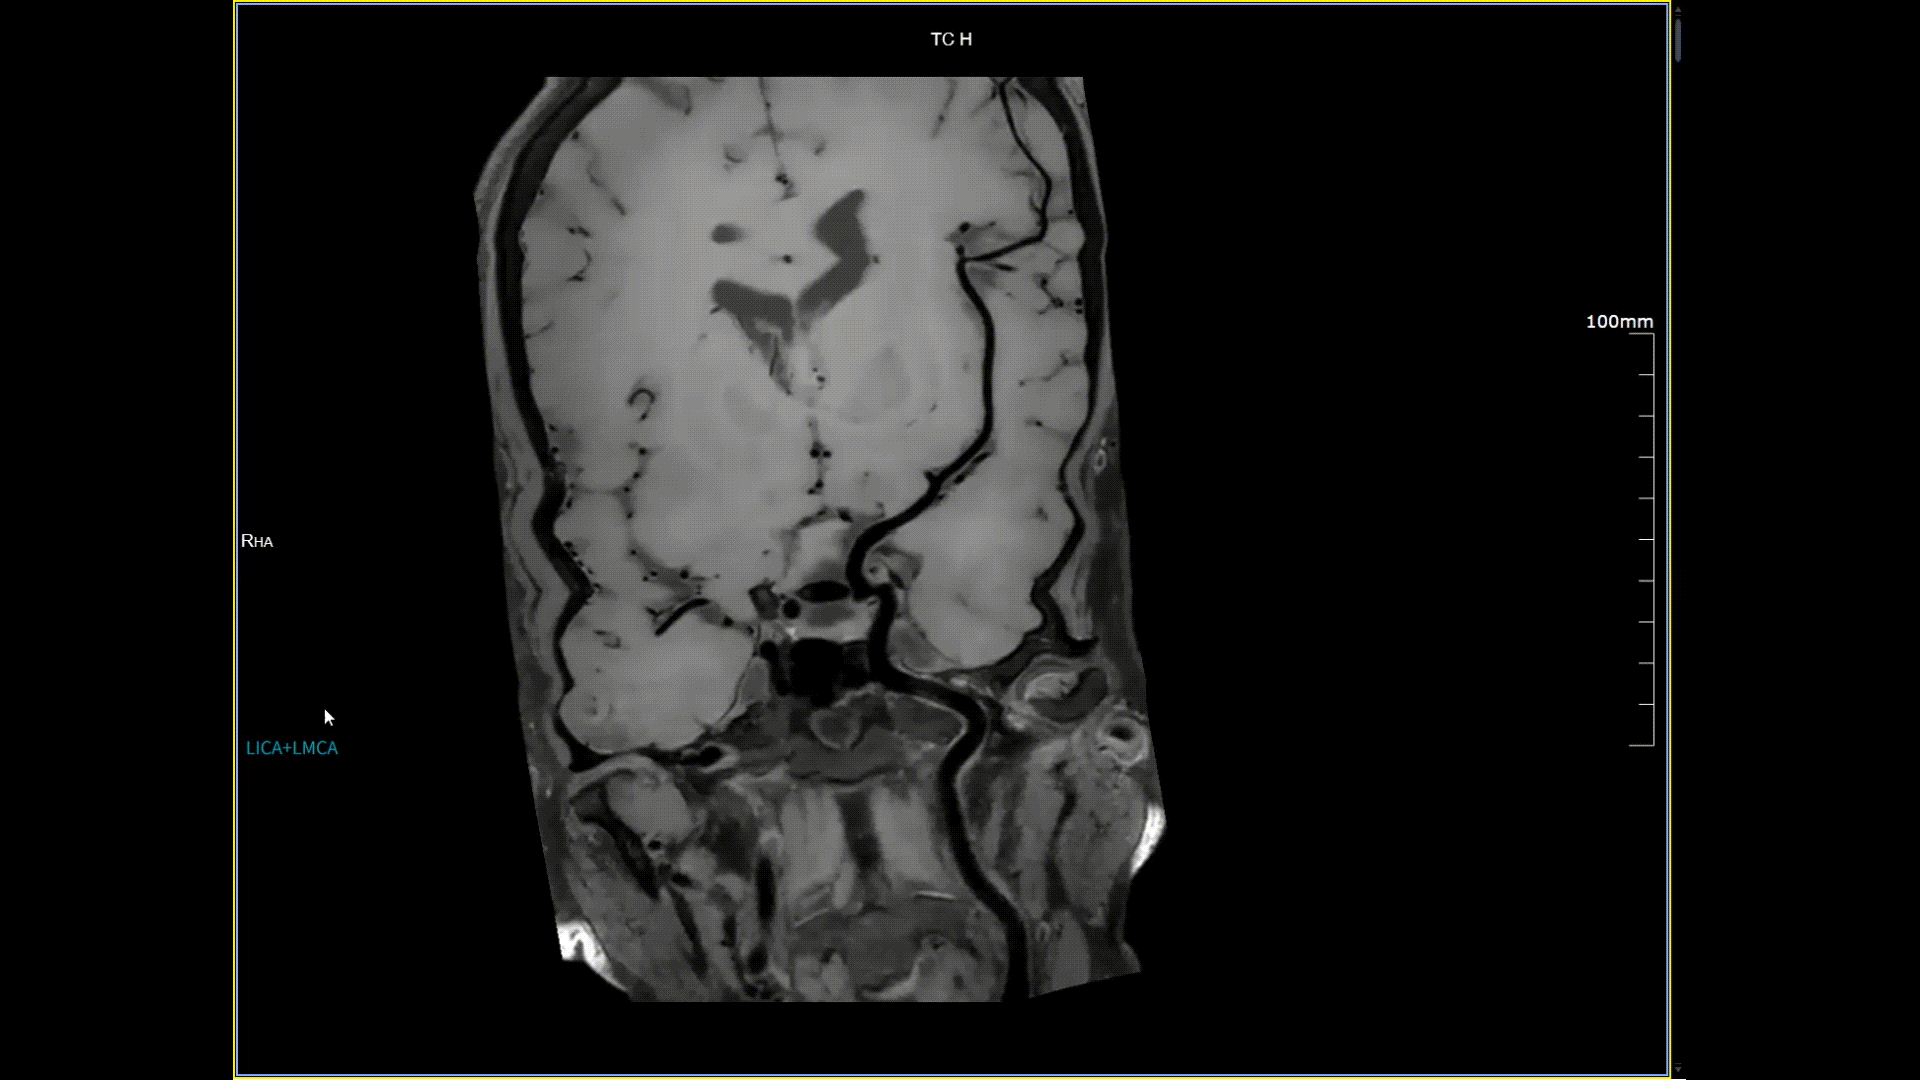

头颈血管斑块,分辨率0.4*0.4mm

11月3日,一名30岁男性在我院接受了河北省首台5.0T超高场核磁共振头颅血管成像检查,图像清晰精准地反映出患者右侧小脑区域的血管畸形情况,该患者对我院的诊疗实力与服务温度给予充分肯定。相较于传统核磁共振,这台设备实现了“超高场全身各部位成像”的技术突破,它以业界领先的超高性能实现亚毫米级超高清成像,尤其在神经、心血管、体腹、关节等部位肿瘤疾病的早期发现、精准评估、个性化治疗方案制定中提供了的强大影像支持,将为全省乃至周边地区患者带来更优质、更精准的医疗服务。

5.0T磁场强度远高于其他设备,使得氢原子核在磁场中的响应信号极大地增强。这就像在安静的房间里能听清细微的声音一样,高信噪比能让医生看到更微小、更模糊的病变结构。例如上述患者的检查,该设备可以呈现0.2x0.2毫米高分辨率的图像以及动态显示血管走行,使得病变血管的细微解剖结构、分布及其与周边脑组织的关系得以直观呈现,为临床医生进行精准诊断并制定后续治疗方案提供了重要的影像学依据。